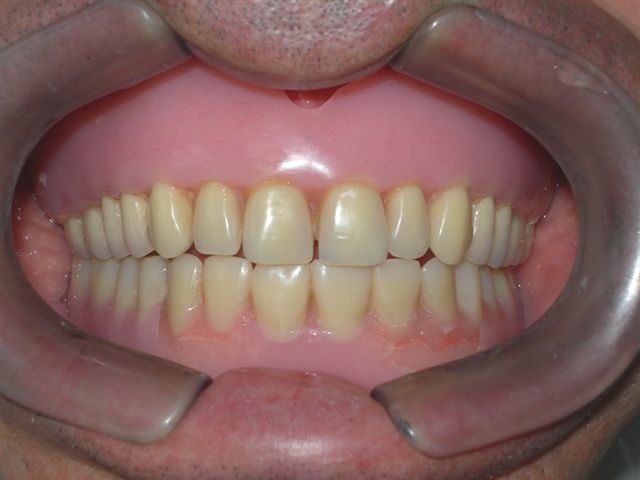

| Próteses antagonistas (VISTA DIREITA) |

Próteses antagonistas (VISTA ESQUERDA) |